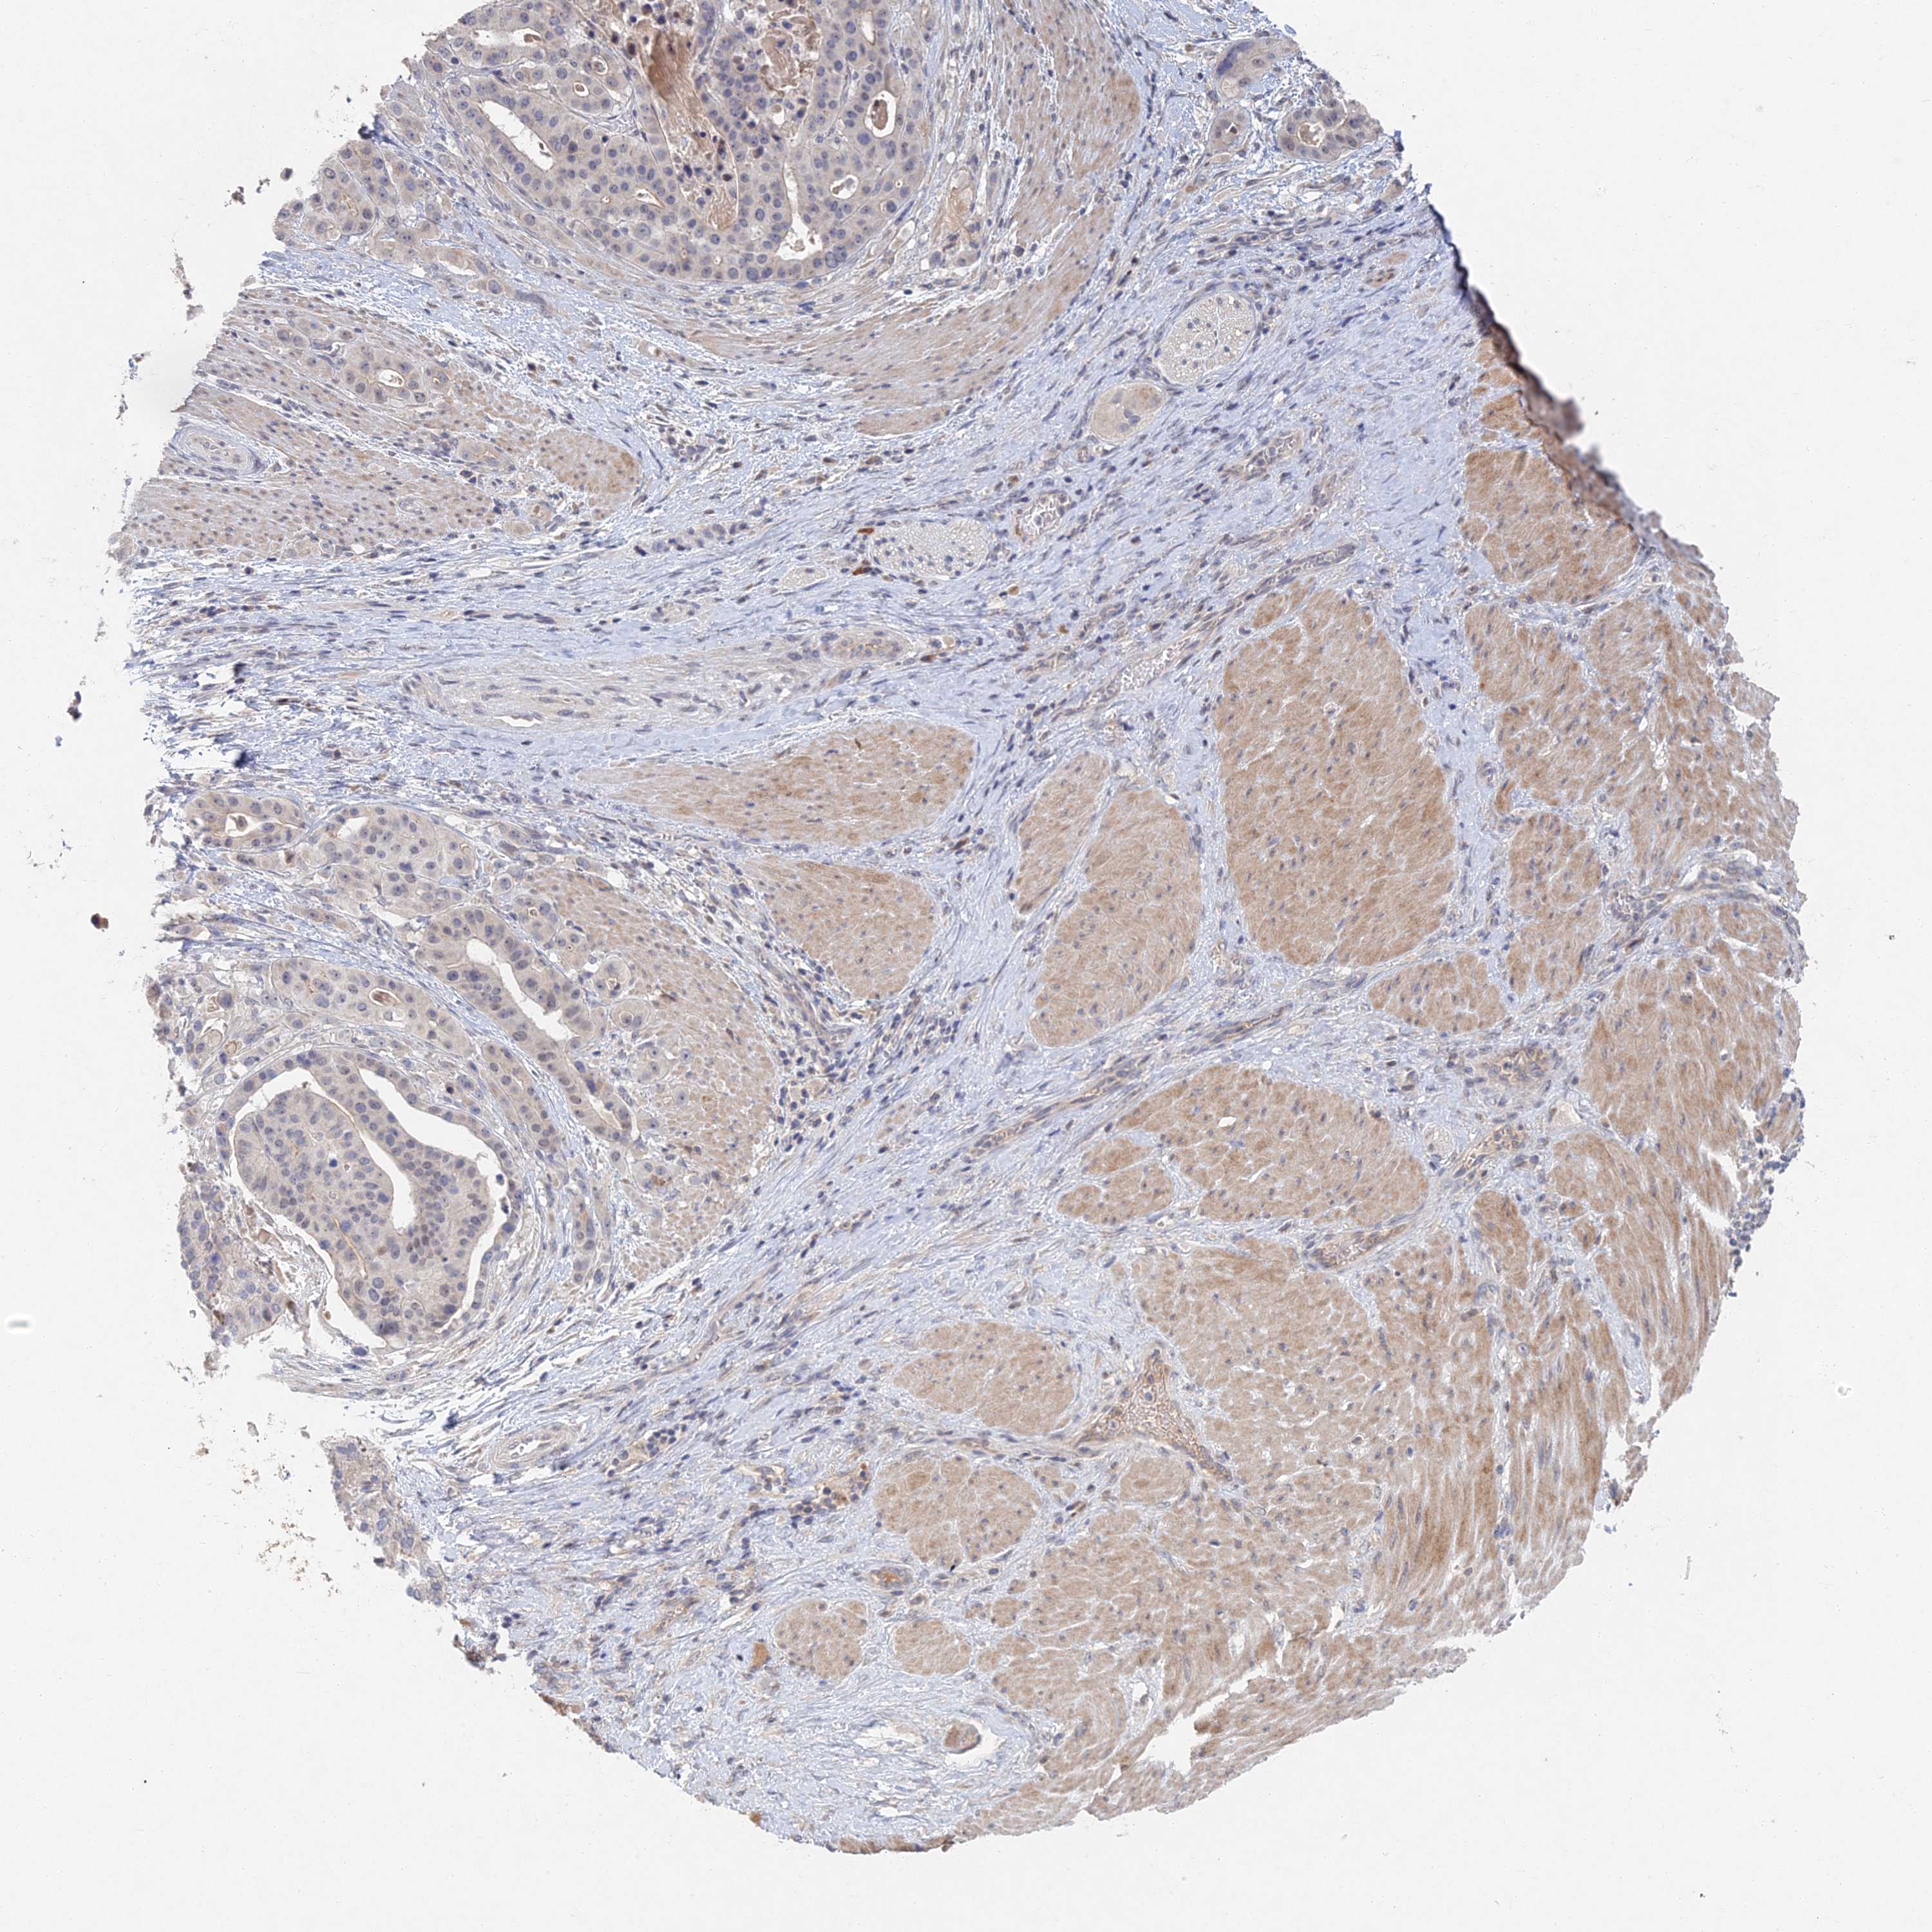

STOMACH CANCER - Protein expressioni

A mouse-over function shows sample information and annotation data. Click on an image to view it in a full screen mode. Samples can be filtered based on level of antibody staining by selecting one or several of the following categories: high, medium, low and not detected. The assay and annotation is described here.

Note that samples used for immunohistochemistry by the Human Protein Atlas do not correspond to samples in the TCGA dataset.

Antibody stainingi

Antibody staining in the annotated cell types in the current human tissue is reported as not detected, low, medium, or high, based on conventional immunohistochemistry profiling in selected tissues. This score is based on the combination of the staining intensity and fraction of stained cells.

Each image is clickable and will lead to virtual microscopy that enables deeper exploration of all samples and also displays staining intensity scores, fraction scores and subcellular localization as well as patient and tissue information for each sample.

Antibody HPA043113

Staining

High

Medium

Low

Not detected

Intensity

Strong

Moderate

Weak

Negative

Quantity

>75%

75%-25%

<25%

None

Location

Nuclear

Cytoplasmic/membranous

Cytoplasmic/membranous,nuclear

Adenocarcinoma, NOS